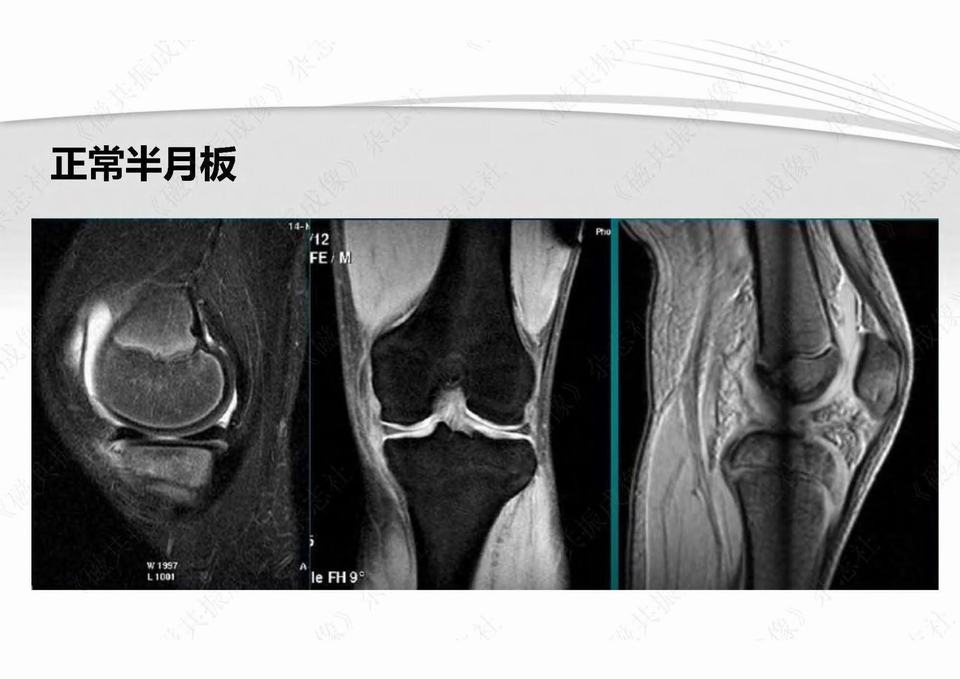

半月板损伤术前及修补术后MR影像学评价